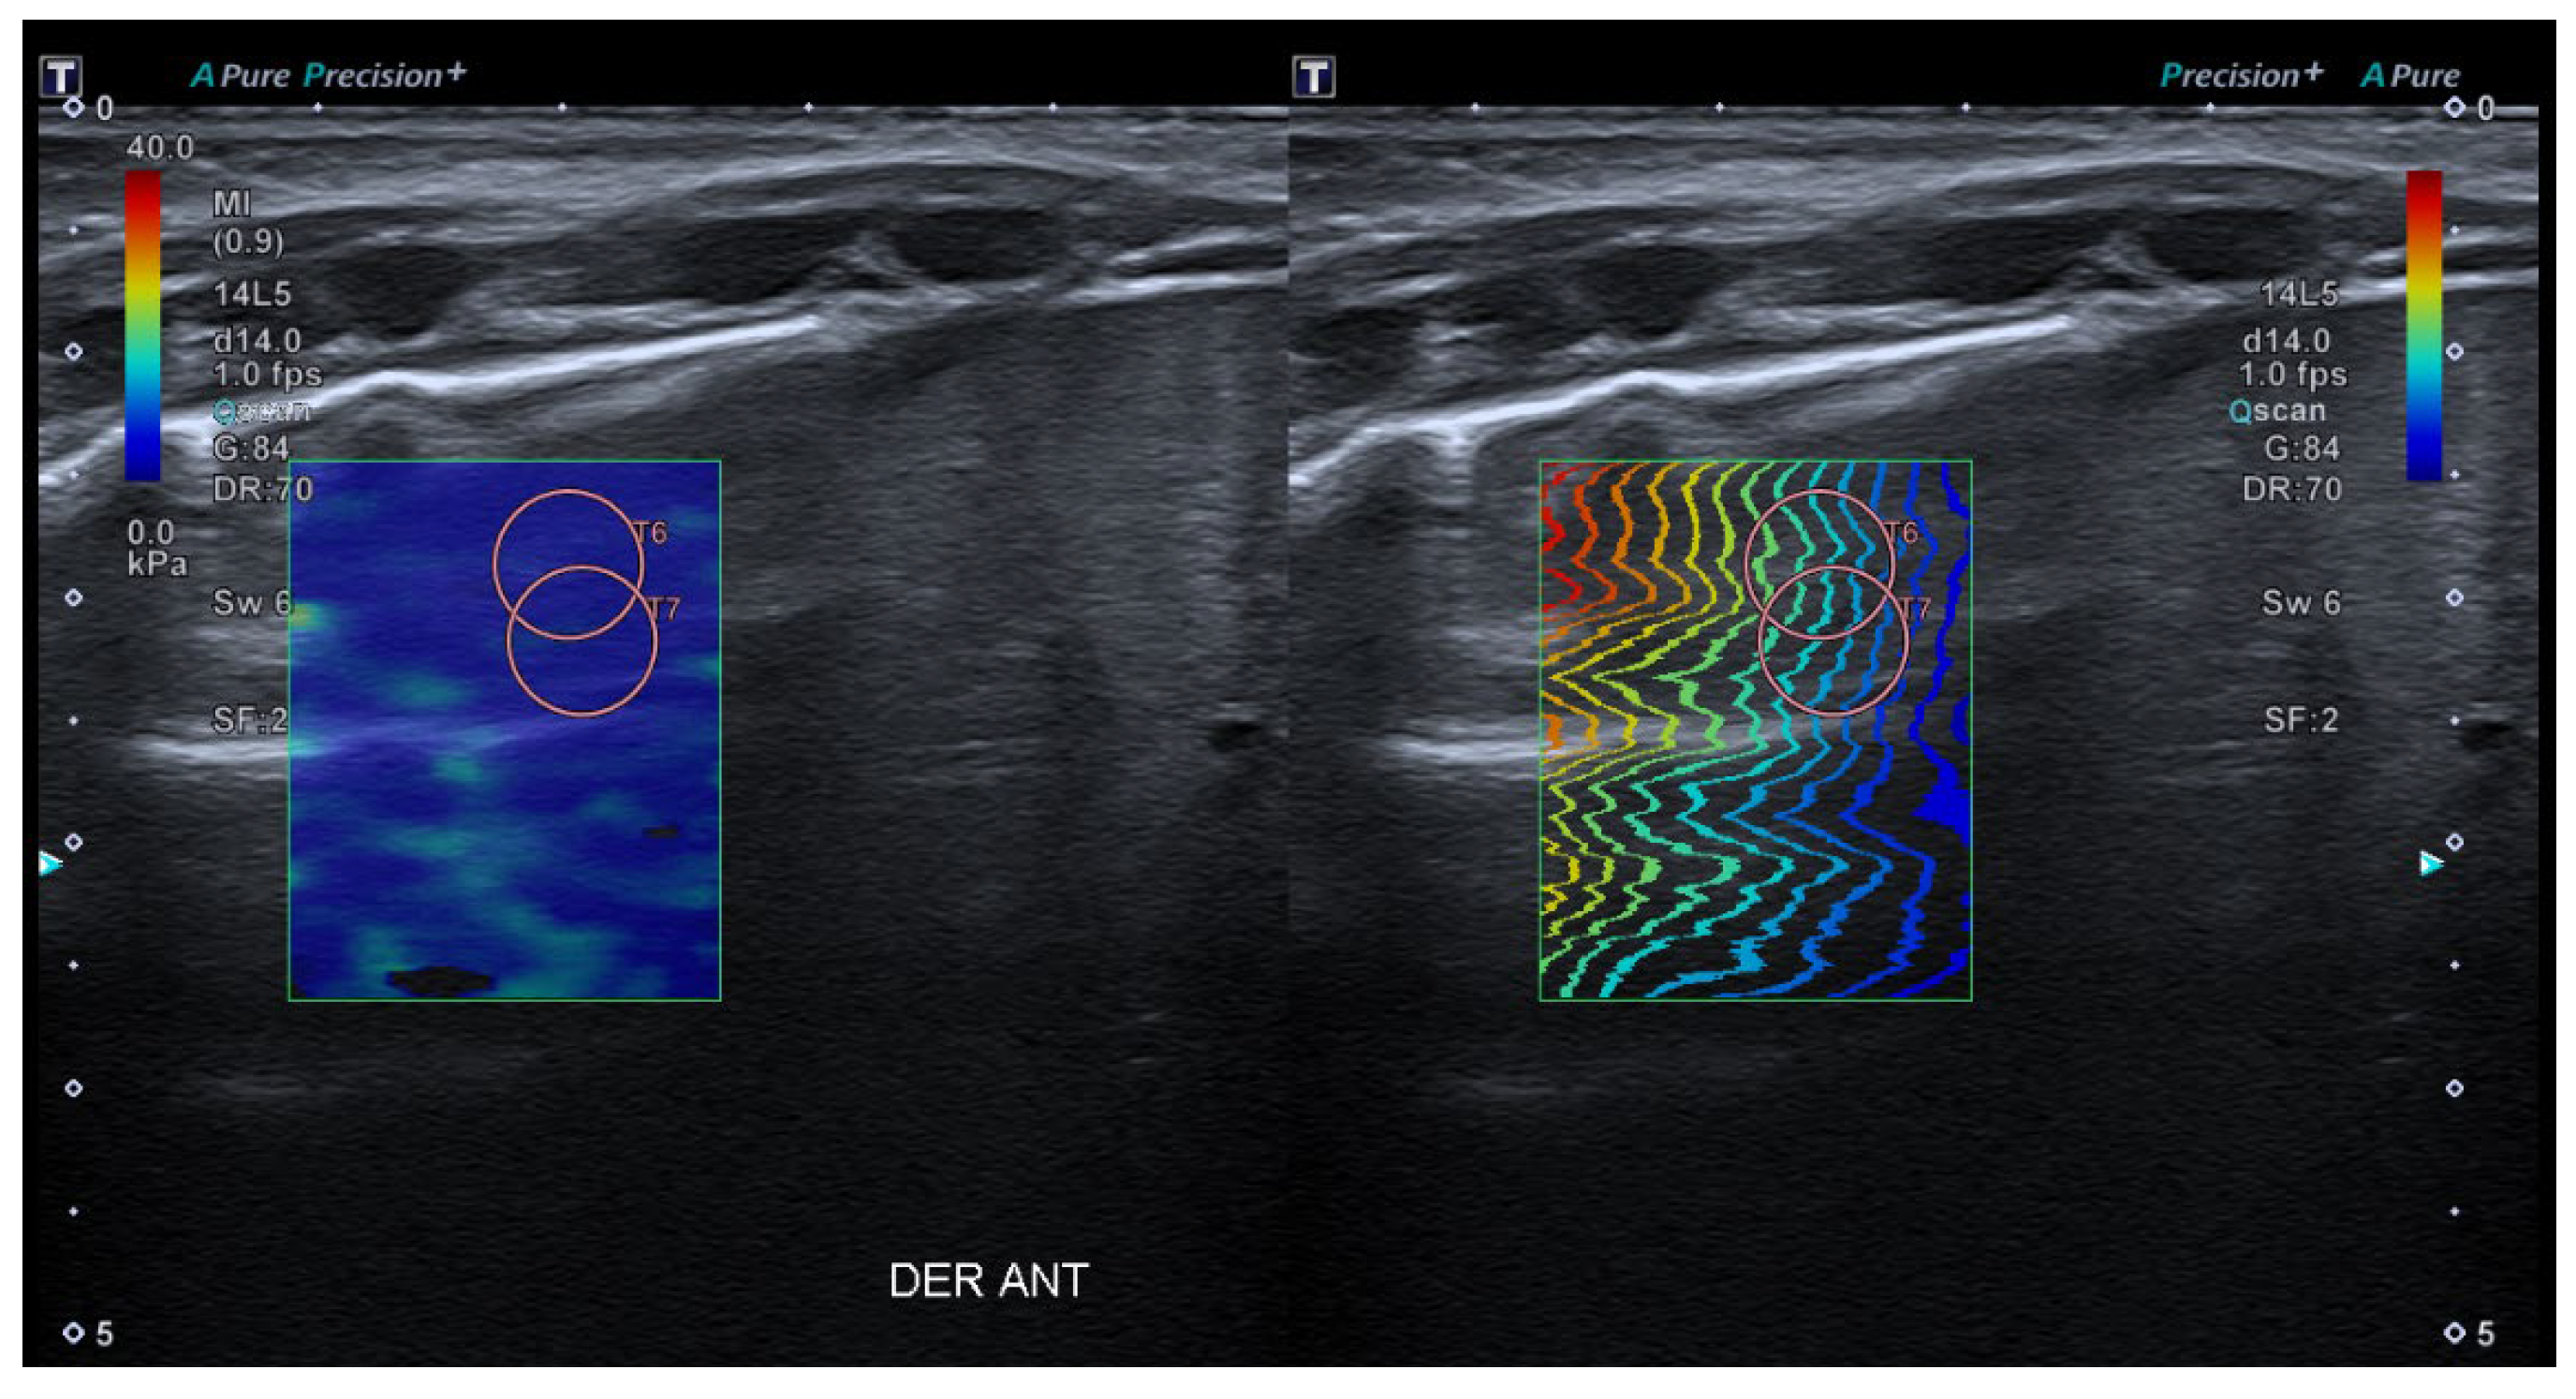

- 2D-Shear Wave Elastography (SWE): This is the latest and newest shear wave imaging technique. Like ARFI or pSWE, it uses acoustic radiation stimulation but, in this case, it rapidly scans multiple focal areas. This creates a virtual cylindrical shear wave cone that allows for the real-time monitoring of shear waves in 2D to measure their velocity, which is displayed on a quantitative colour map superimposed on a B-mode image (Figure 5). SWE has been extensively applied to characterize liver fibrosis [30,31], breast masses [32,33], prostate cancer lesions [34], thyroid nodules [35] and cervical lymph nodes [36]. In these contexts, SWE displayed low variability with respect to SE [37].